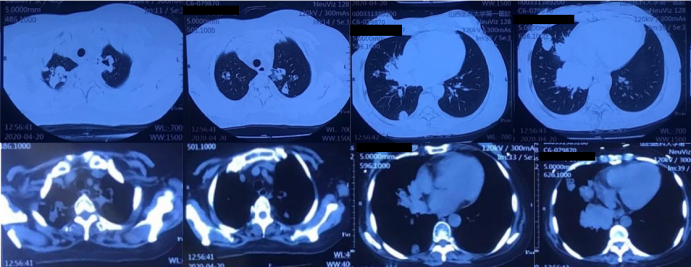

患者半年前因“成人Still病”开始口服激素(醋酸泼尼松片20 mg qd)及环孢素(50 mg bid)治疗,用药期间患者出现咳嗽、咳痰症状,黄白色黏痰,量不多,不易咳出,无胸闷、气短、胸痛、咯血等不适,就诊于北京某医院,完善胸部CT示“双肺多发肿块影及结节影,部分内伴空洞”,该院考虑真菌感染,予口服伏立康唑治疗1周。用药后患者咳嗽、咳痰症状一度缓解。自2020年2月开始,患者咳嗽、咳痰加重,间断出现发热,体温最高可达40℃,伴有畏寒,无寒战、呼吸困难等其他症状,调整激素为早晚各一次(醋酸泼尼松片10 mg/次),但患者体温控制较差,于3月15日(图1)及4月20日(图2)复查胸部CT检查,提示双肺多发肿块影及结节影,部分内伴空洞形成,病灶有增大、增多趋势。为求进一步诊治收入我院。

图2  患者胸部CT(2020-04-20)

胸部CT(2020-03-17):双肺多发肿块影及结节影,较大者大小约为3.7  cm×2.7 cm,部分内伴空洞。胸部CT(2020-04-20)示:双肺多发肿块影及结节影,较大者大小约为9.68 cm×5.4 cm,部分内伴空洞,与前片对比,病灶明显增大、增多;心包少量积液。